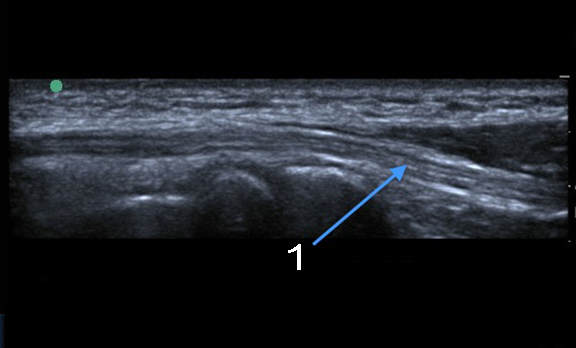

肘部管長軸の画像

尺骨神経長肘部管